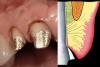

A clinician is faced with 3 options for for margin placement when considering an anterior esthetic restoration: supragingival, equigingival (ie, even with tissue), and subgingival.1 The supragingival or equigingival margin will have the least impact on the periodontium and, classically, was only used in nonesthetic areas because of the stark contrast in color and opacity of traditional restorative materials. With the advent of adhesive dentistry, resin cements, and more translucent restorative materials, the ability to place supragingival or equigingival margins even in esthetic areas is now a reality (Figure 1 and Figure 2). The primary requirement of a material to enable its use in esthetic areas supra- or equigingivally is a high level of cervical translucence. Materials such as feldspathic porcelain, as well as pressable ceramics, meet this requirement. Consequently, whenever possible, these restorations should be chosen not just for their esthetic advantages, but for their favorable periodontal impact as well. The greatest biologic risk occurs when placing subgingival margins.2

Figure 1  View of 4 porcelain veneer preparations with the margins placed at the level of tissue.

Figure 1

Figure 2  Note the invisibility of the marginal line in the completed veneers, even though the margin has not been carried below tissue.

Figure 2